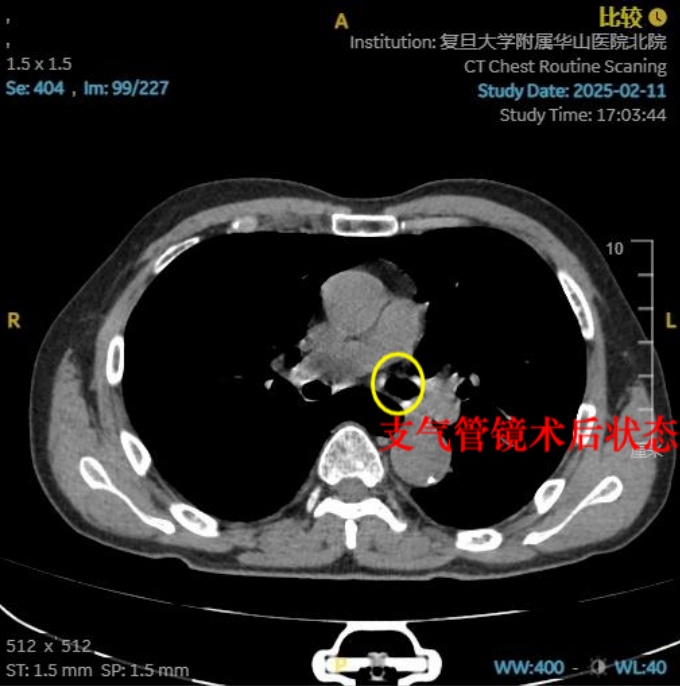

医护团队立即为蔡老伯安排支气管镜取出异物。然而由于虾体有小拇指大小,虾壳表面光滑,虾肉部分因煮熟后质地松软,再加上虾头的虾枪部位尖锐锋利,取出过程中极易划伤气道黏膜,这些都给夹取带来了不小难度。最终,经过半个多小时的紧张手术,整只河虾被成功取出,老人呼吸困难的症状马上缓解。“非常感谢医护人员,因为这条命是他们救回来的!”老人感激地说。